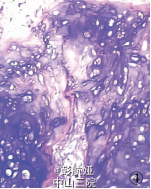

患者女性,37岁。因渐进性头痛2年、右侧头面部及肢体麻木3个月入院。查体:患者意识清晰,双侧视乳头水肿,右侧头面部及肢体感觉减退,右上肢及下肢肌力4-5 级。CT检查,左顶叶见一高密度影肿块,9.5cm*7cm*6.5cm,边缘清楚,中央可见钙化及囊性变(图1),肿块体积巨大,脑中线结构右移(图 2),MRI 显示肿块呈不均匀长T1、长T2信号,GD-DTPA 延迟期有强化效应。CT、MRI 诊断:左顶叶占位,性质待定。临床以左顶叶肿瘤行手术切除治疗,术中见肿块位于中央沟内,与大脑镰相连,大脑镰右移,左顶叶受挤压显著,肿块质硬,活动可,与脑组织无粘连,予肿块完整切除,标本送病理检查。术后患者头面部及肢体感觉恢复,肢体肌力增加,在随访中。